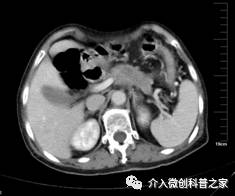

中晚期胰头癌侵及胆总管行胆道支架植入治疗

(梗阻性黄疸即可解除)